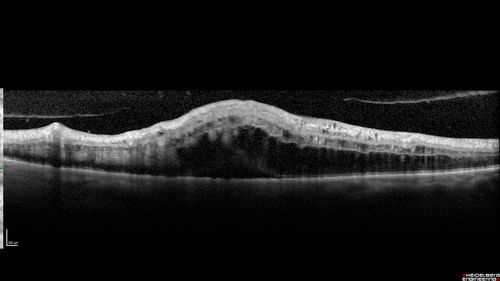

Central Retinal Vein Occlusion with Macular Edema

74 year old female The vision in the left eye has gotten worse over the last 3 weeks.

VA OD: Dcc20/25

VA OS: DccCF 3ft

IOP: TP: OD:16 OS:14

Vision improved to 20/40 in 3 months with monthly Aflibercept